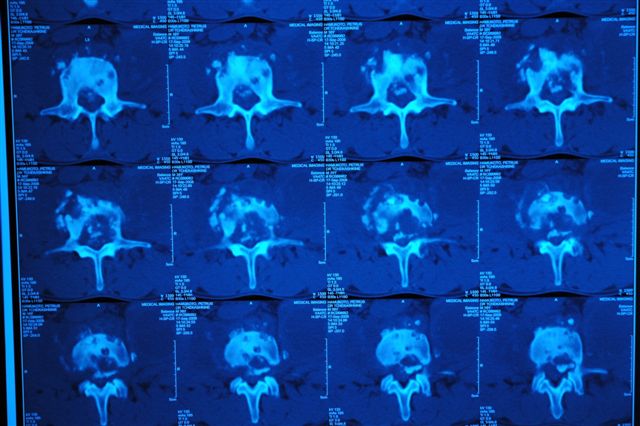

[Ortho] туберкулёзный спондилит

Обратился мужчина 40 лет с постоянными болями в поясничном отделе позвоночника, не купирующиеся аналгетиками, противовоспалительными препаратами

Соматически здоров, неврологического дефицита в конечностях, нарушений функции тазовых органов нет.

СОЭ - 4 , С-  реактивный белок -1